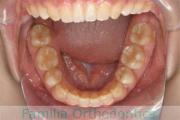

No.23V-478

- 叢生

- 30歳

- 男性

- 抜歯部位

- 上:

- 44済

- 下:

- 8558済

- 主な使用装置:

- FEA 022

- 治療にかかった費用:

- 76万円

右上の歯が重なっているところが邪魔になるとのことで矯正治療を始められた患者さんで、札幌から転院されました。当院で約1年半、15回程度の通院が必要でした。叢生(でこぼこ、凹凸、ガタガタ)が強く、後戻りのリスクが高いケースです。